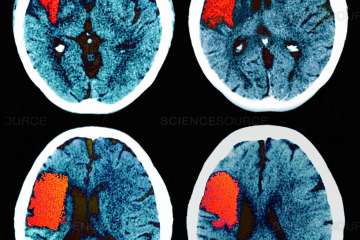

Thrombectomy – pulling a clot out of a blocked brain artery – is now the gold-standard treatment for acute ischemic stroke and was invented at UCLA.

Brain Scan